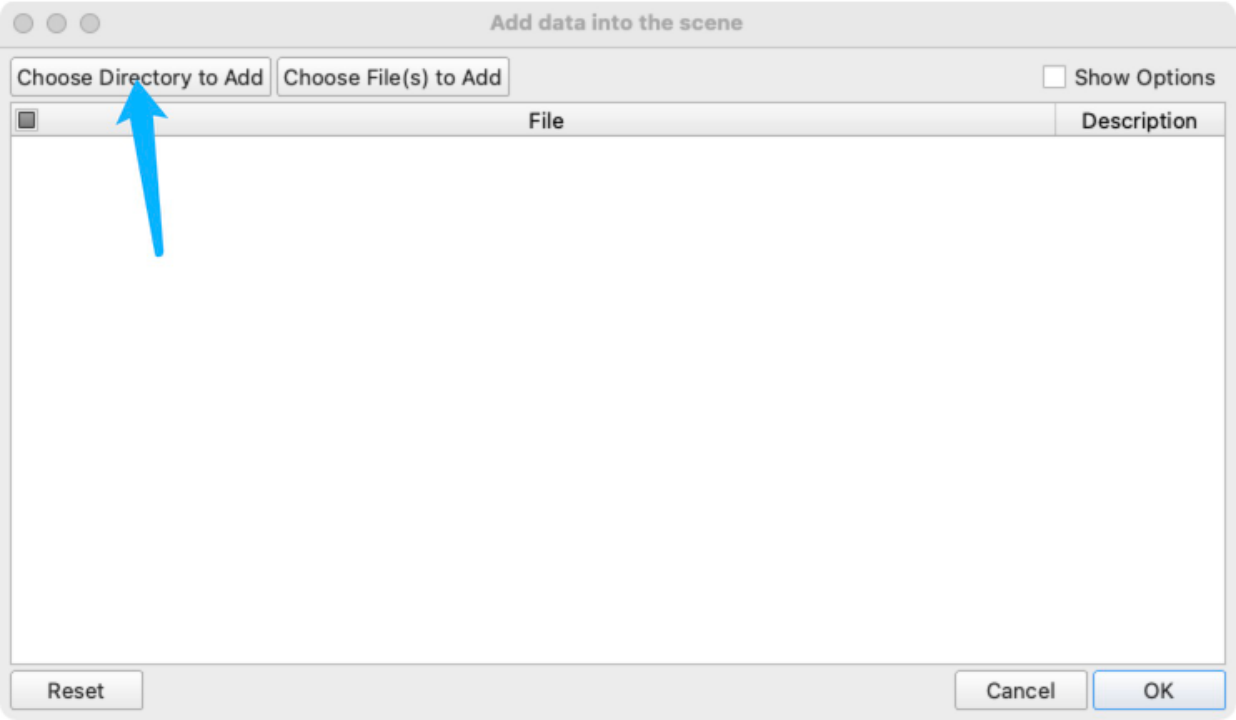

- 导入数据: